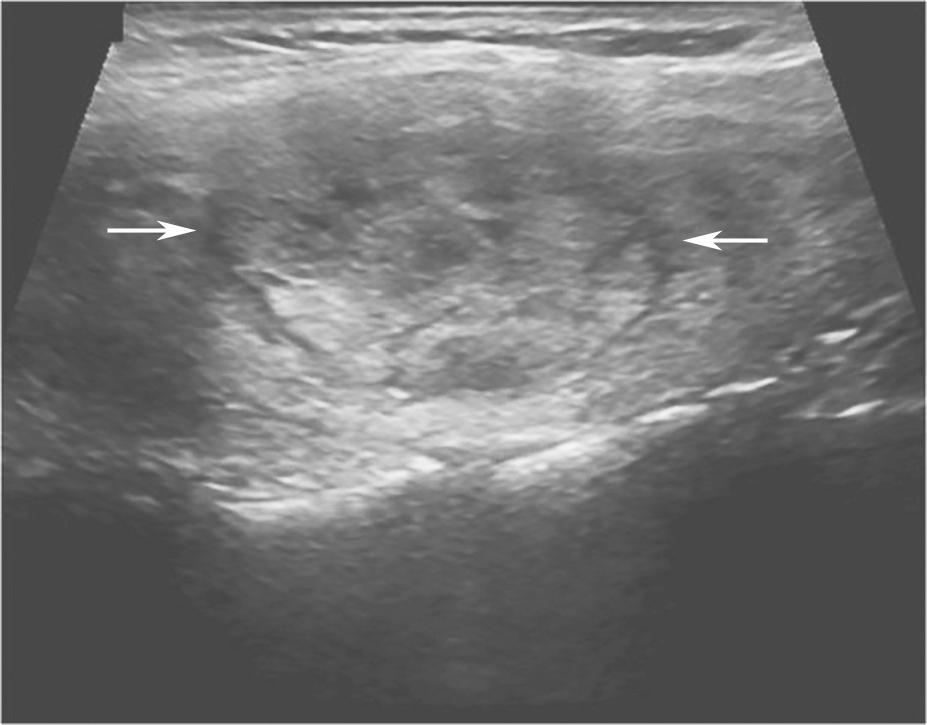

甲状腺滤泡癌和滤泡腺瘤在超声上鉴别有一定困难,即使是FNA细胞学也很难鉴别。但有报道认为:与甲状腺乳头状癌不同,甲状腺滤泡癌常为等回声或高回声,微小钙化很少见,病变多伴有厚薄不一的低回声晕或者局部低回声晕。彩色多普勒血流信号丰富也是该类病变的特点之一(图11、图12)。

图11右侧颈部纵切面:甲状腺右叶中部中等回声(箭头所示):内部回声不均伴厚薄不一低回声晕